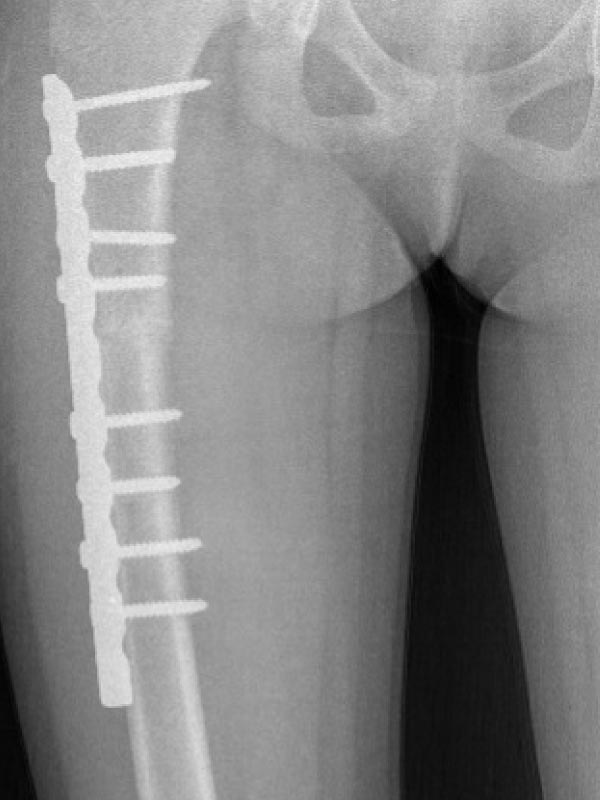

Caso No. 6 - Hemimelia tibial derecha

Preoperación

Posoperación 1

Hemimelia Tibial Derecha

Diagnóstico: Agenesia de peroné + Acortamiento de extremidad inferior derecha

Primera cirugía: Fijación externa Ilizarov para alargamiento femoral

Posoperación 2

Rehabilitación

Segunda cirugía: cambio a fijación interna (7cm de alargamiento)

Paciente rehabilitándose y aun pendiente el alargamiento de la tibia derecha